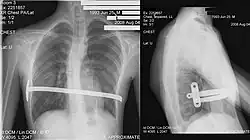

Technique de Nuss

La technique chirurgicale mini-invasive de Nuss, plus récente[16], consiste à introduire une ou deux barres à l'intérieur de la cage thoracique du patient et à les maintenir à l'aide de stabilisateurs, le tout sous contrôle thoracoscopique. Cette intervention est privilégiée pour les jeunes personnes n'ayant pas fini leur croissance (idéalement vers 15 ans, pour une ablation des barres à 18 ans, âge de fin de croissance) et possédant donc encore une structure de cage thoracique relativement souple. L'opération redresse instantanément le thorax mais empêche la pratique de sport pour un délai de 3 mois et interdit les sports de contact (rugby, karaté…) pendant toute la durée durant laquelle le patient porte la ou les barres. Cette technique nécessite une durée d'hospitalisation d'une semaine dont 4 à 5 jours sous péridurale. Plus cette opération est pratiquée tôt, moins les douleurs physiques sont grandes (croissance des cartilages). Le matériel est généralement enlevé trois années après avoir été mis en place, une fois que la structure osseuse est solidifiée (transformation des cartilages osseux en os solides, due à l'âge). Le rapport risques/bénéfices de la technique de Nuss est cependant remis en cause du fait de la gravité des complications médicales qui peuvent résulter d'un déplacement de la barre (notamment des perforations cardiaques ou des interruptions de la veine cave)[17].